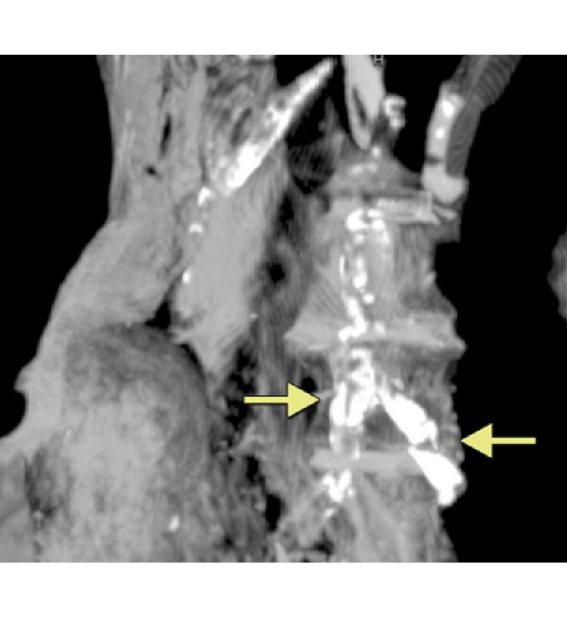

3,500 Year Old Aortic Atherosclerosis From Atherosclerosis in Ancient Egyptian Mummies: The Horus Study https://www.sciencedirect.com/science/article/pii/S1936878X11000660?via%3Dihub#fig2

So far, I have spoken about hard tissues, but mummies contain large amounts of well-preserved soft tissues as well. The frequency of hardening of the arteries in ancient Egyptians was 56%, as evidenced by an examination of their mummified bodies. Sixteen mummies who received full-body computed tomography scans had hearts or arteries preserved enough to study. Of those, nine had evidence of blockage from atherosclerosis. The findings suggest that the curse of the mummy may have been a grain-based, low-protein diet. 5 Heart disease is blamed on saturated fat and meat, but it seems vegetarian grain-based diets are more to blame in the case of the ancient Egyptians.